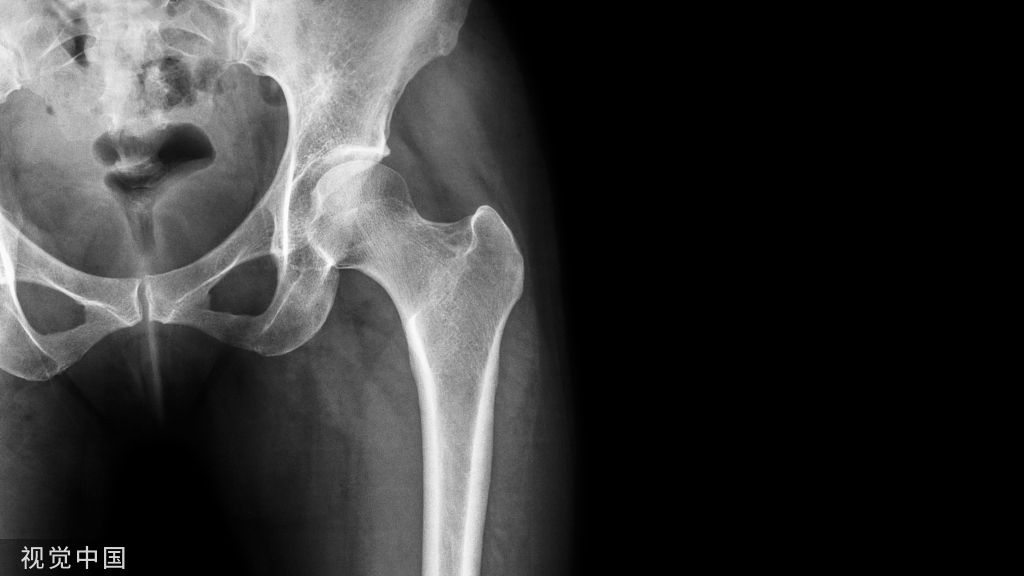

(一)地图样破坏  地图样破坏是指肿瘤组织在一个局部呈团块状生长造成界限清楚的骨质破坏(图 1、图 2、图 3、图 4)。

病灶可位于骨的中心或一侧部位,呈圆形、卵圆形密度减低区,与正常骨质分界清晰,边缘可有或无硬化带围绕,骨的形态无变化,病灶内可完全透亮或可见粗细不均、大小不等的残留骨嵴,内缘可光滑或呈分叶状压迹。

地图样破坏见于大多数良性肿瘤和肿瘤样病变如单纯性骨囊肿、骨纤维结构不良、血管瘤等、也可见于部分恶性骨肿瘤如骨转移瘤、骨髓瘤等。

图 2  地图样破坏:骨纤维结构不良

图 3  地图样破坏:骨内脂肪瘤

图 4 地图样破坏:骨转移瘤